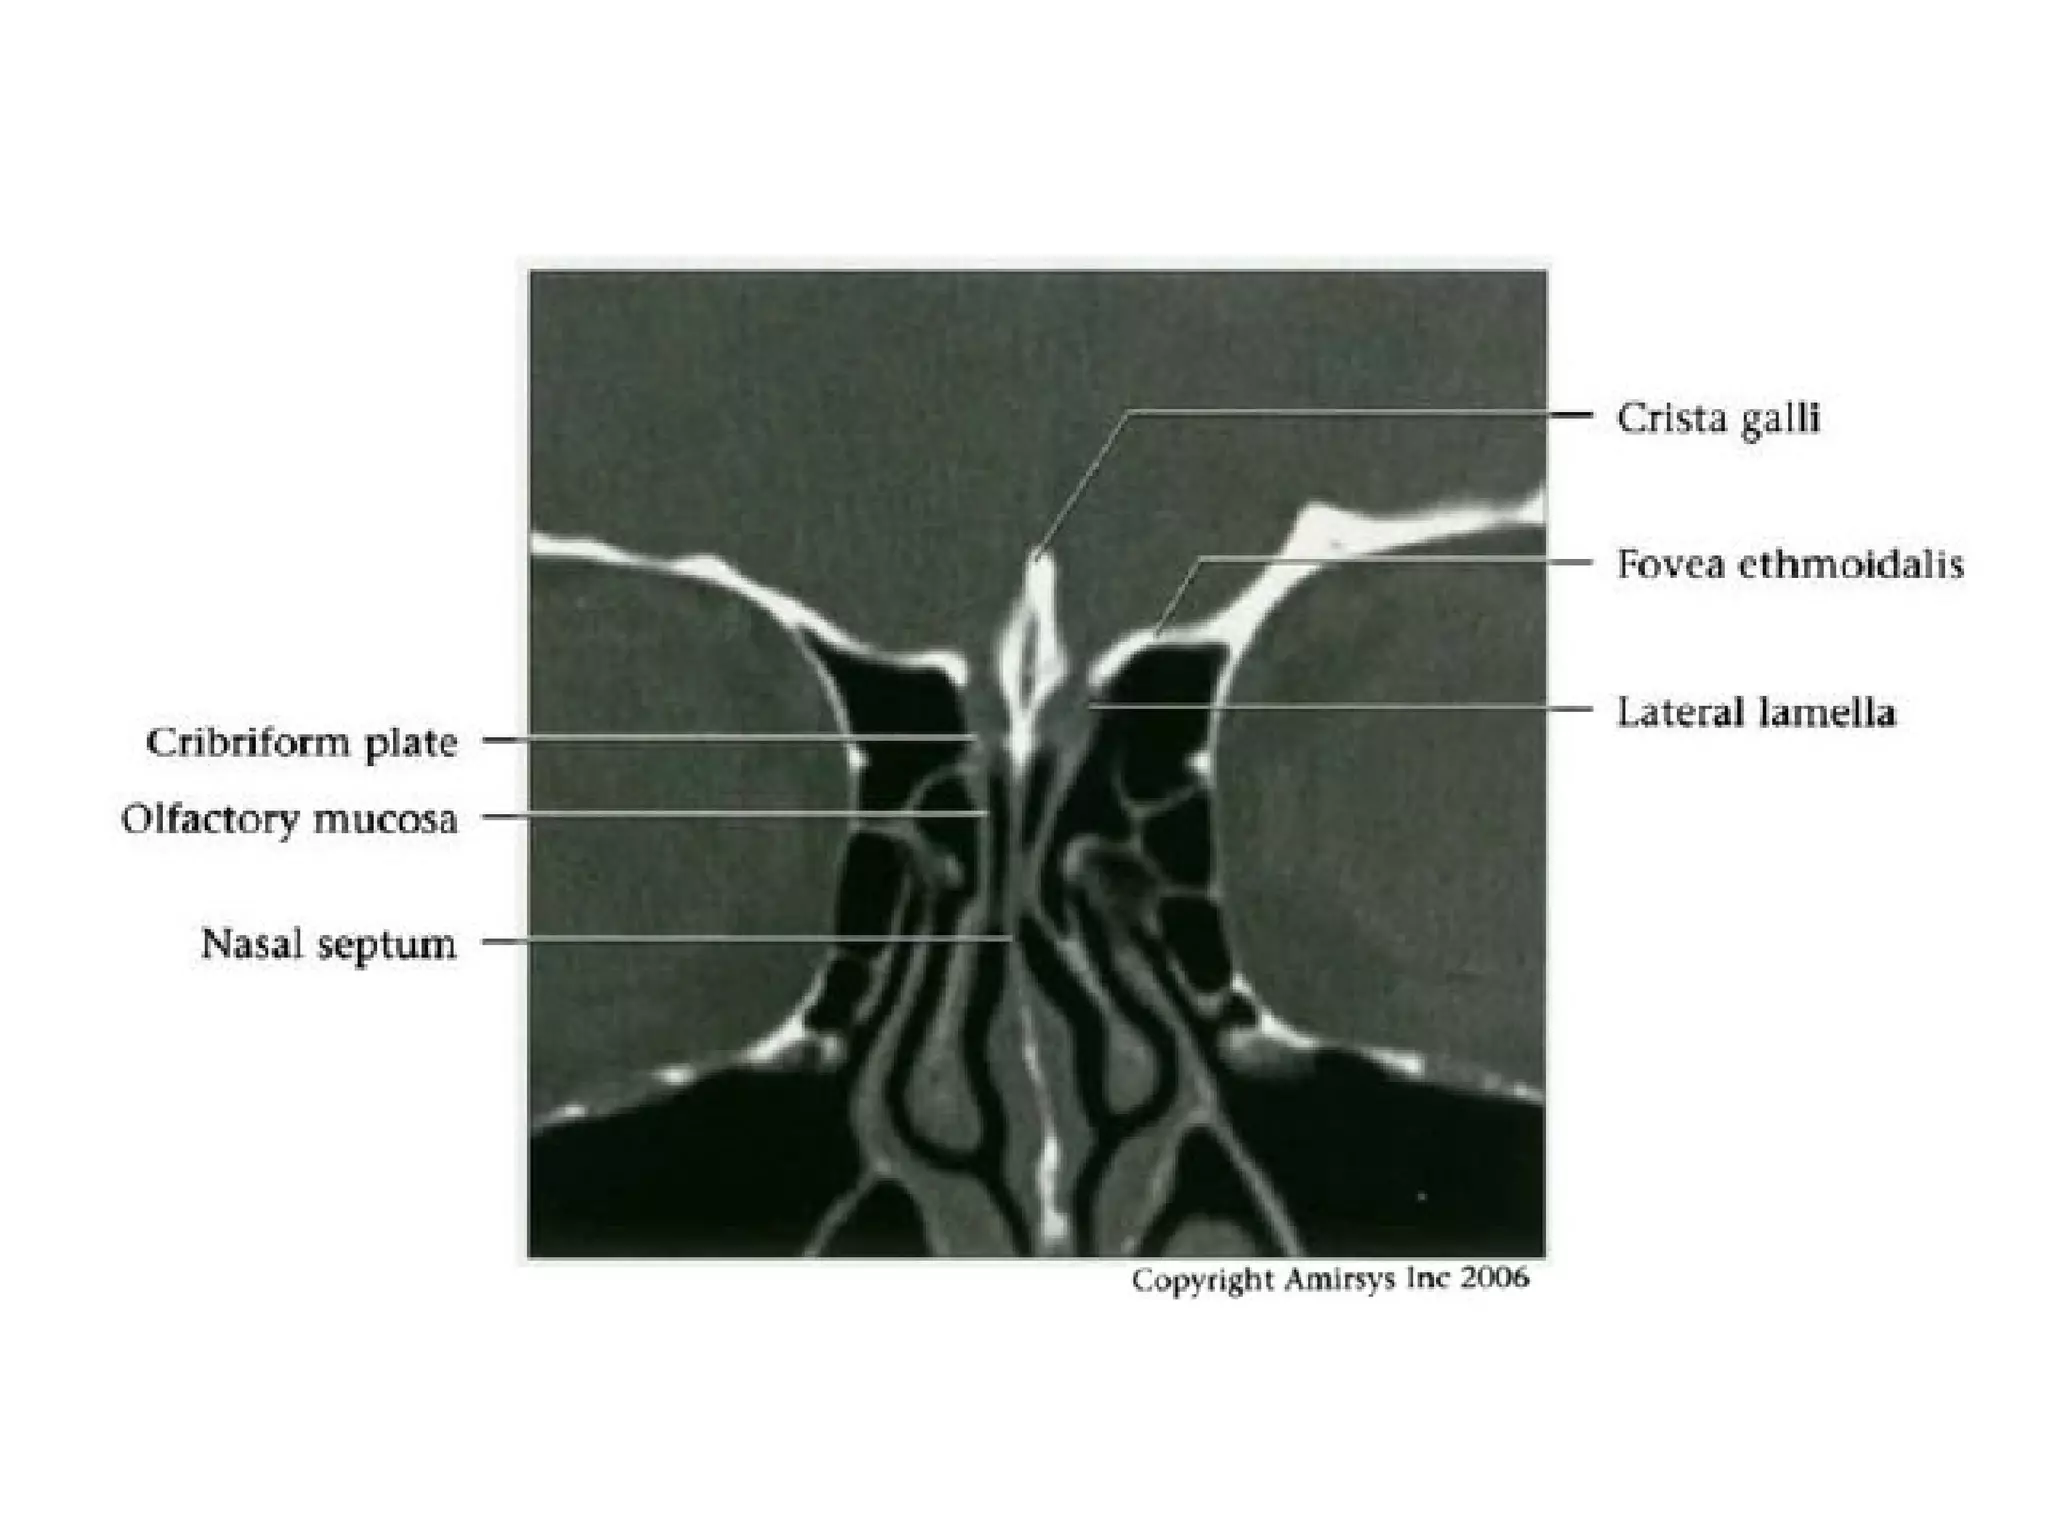

CN1: Nasal Epithelium

• Approximately 2 cm² nasal epithelium in roof of each

nasal cavity

- Extends onto nasal septum and lateral wall of nasal

cavity including superior turbinates

CN1: Transethmoidal Segment

• Central processes of bipolar receptor cells

traverse cribriform plate to synapse with

olfactory bulb

• Hundreds of central processes traverse

cribriform plate as unmyelinated fascicles

(fila olfactoria)

- Fila olfactoria are actual olfactory nerves

- Each side of nasal cavity has - 20 fila

olfactoria

CN1: Imaging Recommendations

• Coronal sinus CT is best study for isolated

anosmia

- Identifies nasal vault and cribriform plate

lesions

CN1: Imaging "Sweet Spots"

• Intracranial: Include anterior cranial fossa

floor and medial temporal lobes

• Extracranial: Include nasal vault and

cribriform plate